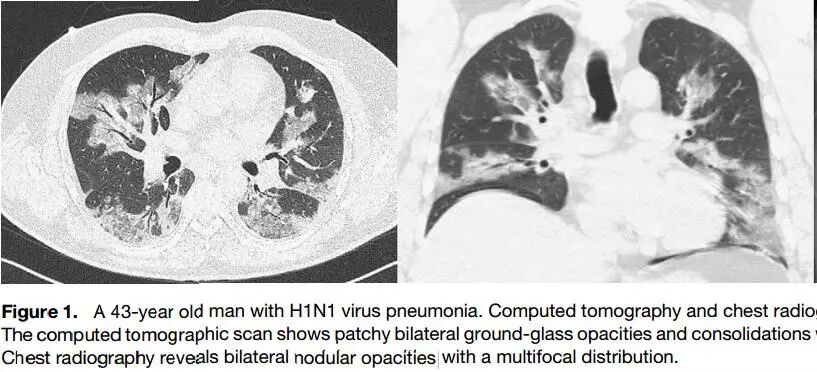

文献6:Henzler T, Meyer M, Kalenka A, et al. Image findings of patients with H1N1 virus pneumonia and acute respiratory failure[J]. Academic Radiology, 2010, 17(6):681-685.

乍一看,胸片是多发结节阴影。下面是CT:

沿着两侧肺门分布,乍一看,像肺水肿,但是心脏不大,下肺胸膜下病灶不少,发热、气促、磨玻璃,还是考虑病毒性肺炎。